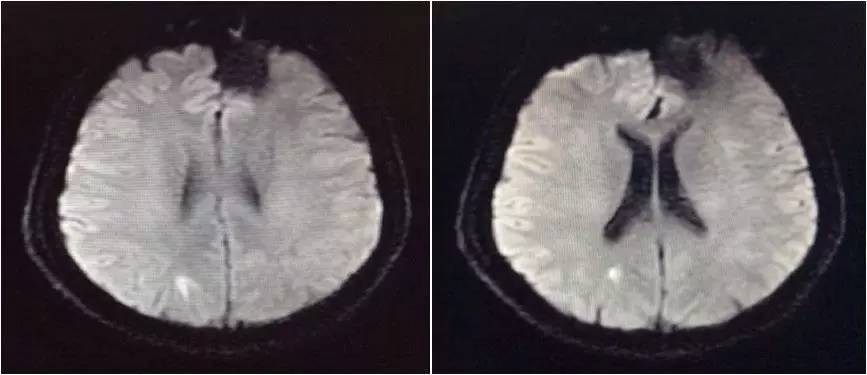

▼头颅MRI

2.脑脊液改变不除外结核感染,但头MRI改变非典型结核影像。左额叶病灶似以脑外为主,波及对侧及额窦,不排除慢性感染病灶急性破入蛛网膜下腔。左额叶病灶与脑脊液信号等信号,DWI也为低信号,说明非急性病变。

嗯,我们用的是国产的头孢曲松,没有进口的罗氏芬。DWI的高信号可以用血管炎解释吗?

血管炎都是多灶的,那个高信号太局限了,就是核心病灶周围的组织反应。不像血管炎。

真菌或结核可以引起脑底血管深穿支的炎症,有类似腔梗的影像改变。